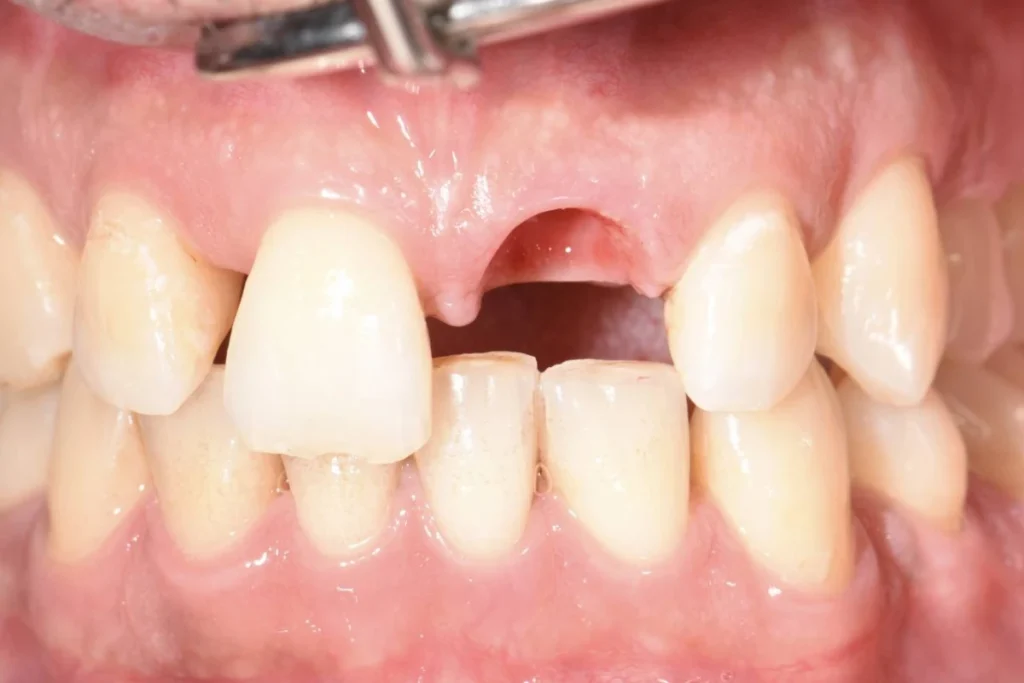

Mr M., 33 ans, se présente à la consultation suite à un traumatisme survenu à la boxe. La facette dentaire réalisée il y a plusieurs années par un confrère a été perdue après un coup encaissé au visage.

Le patient souhaite remplacer sa prothèse pour pallier au préjudice esthétique en urgence. Malheureusement, la dent présente une carie qui ne permet plus de conserver cette dent. Une dent provisoire est réalisée au cabinet afin de gérer l’urgence esthétique évidente et de permettre au patient de réfléchir aux soins proposés « à tête reposée » 🙂

Après un traitement parodontal initial nous permettant de mettre l’environnement buccal dans les meilleures conditions pour l’intervention, nous décidons avec le patient de planifier la chirurgie. Un protocole d’extraction implantation et mise en esthétique immédiate est décidé afin d’éviter au patient le port d’une prothèse amovible.

Le patient repart du cabinet avec une couronne fixée à l’implant tout juste mis en place! En contre partie, le patient devra faire l’effort de ne pas solliciter sa dent lors des repas afin de laisser l’implant s’ostéo intégrer (se souder) à l’os.